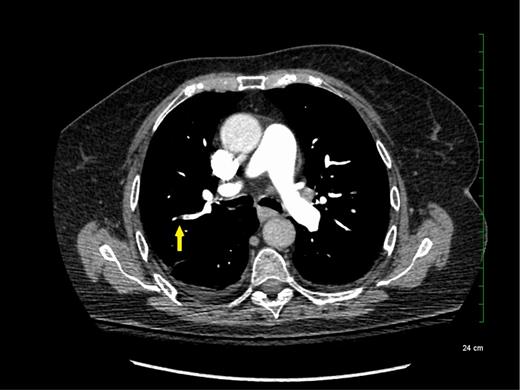

The reported increased incidence of PE diagnosis since the introduction of multirow detector CTPA seems to be correlated with an increase in the diagnosis of PE localized in the subsegmental pulmonary arteries without involvement in larger-order vessels (eg, segmental pulmonary arteries) (see Figure 1). A systematic review and meta-analysis of the literature reported that the rate of SSPE diagnosis among patients who underwent single-row detector CTPA was 4.7% compared with 9.4% for those who underwent multirow detector CTPA.6 Interestingly, the rate of SSPE diagnosis also seems to be increasing with the number of detectors used for PE diagnosis. These rates are reported to range from 7% to 15% in patients undergoing 4-row to 64-row detector CTPA, respectively.6 Similarly, a cohort study using 64-row detector CTPA reported a rate of SSPE as high as 12% among patients with confirmed PE.7 With further advancements in technology, reported rates of SSPE may increase, highlighting the importance of addressing this important knowledge gap.

Subsegmental pulmonary embolism on computed tomographic pulmonary angiography.

Although SSPE diagnoses are increasing with advancements in technology, the true incidence of SSPE remains unclear. It is unknown whether these filling defects reported by radiologists are actual thrombus or artifacts. Interobserver agreement between radiologists was shown to be low for the diagnosis of SSPE in the emergency room (κ = 0.38; 95% confidence intervals [95% CIs], 0.0 to 0.89).8,9 Previous studies reported that up to 59% of SSPE diagnoses made clinically were actually false positives upon reinterpretation by a thoracic or more experienced radiologist.10,11 Another study including reinterpretations by 5 radiologists showed that for SSPE diagnosis, at least 1 radiologist disagreed with the initial interpretation in 60% of the cases.12 Given this variability in the certainty of SSPE diagnosis, it is important for clinicians to review the CTPA results and confirm the diagnosis with a thoracic or experienced radiologist to avoid exposing patients to anticoagulant therapy for an artifactual finding.